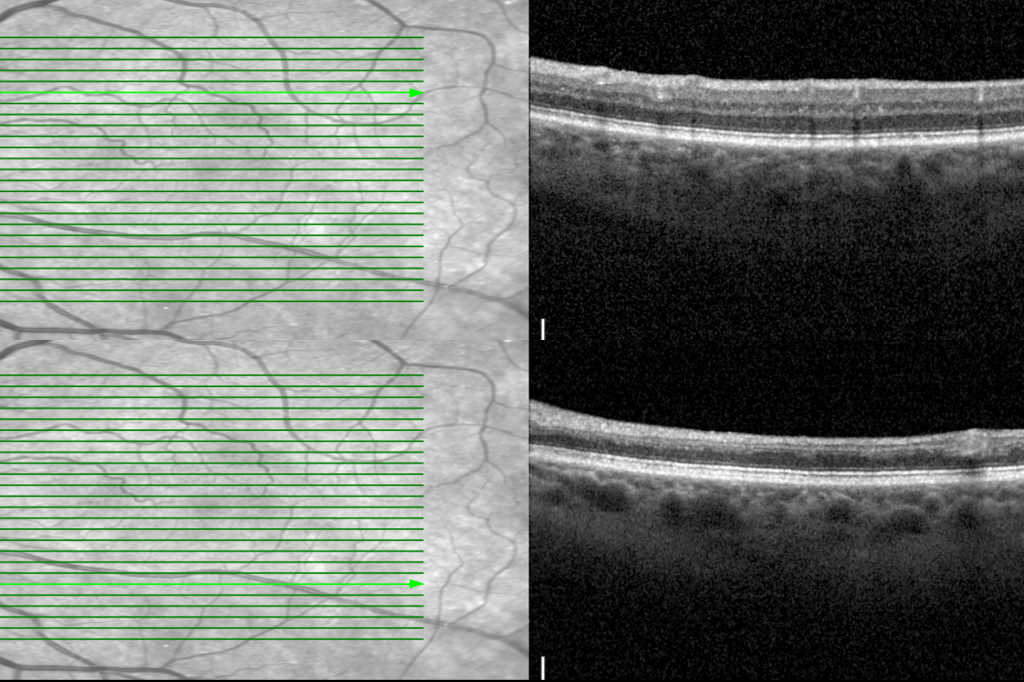

Central retinal artery occlusion (eye stroke). Credit: Dr Gopal Bisht

The protocol, developed by researchers at the New York Eye and Ear Infirmary of Mount Sinai (NYEE), uses optical coherence tomography (OCT) when a patient with suspected central retinal artery occlusion enters the medical system. “This reduces the need for onsite ophthalmology consults, which are often not immediately available,” explained Dr Richard Rosen, head of the Retina Service at Mount Sinai. OCT images are then sent to remote, on-call retinal specialists who can make an instant diagnosis. If they confirm an eye stroke diagnosis, the vascular interventional neuroradiologists can then deliver an infusion of tissue plasminogen activator (tPA) into the blocked ophthalmic artery, said the research team.